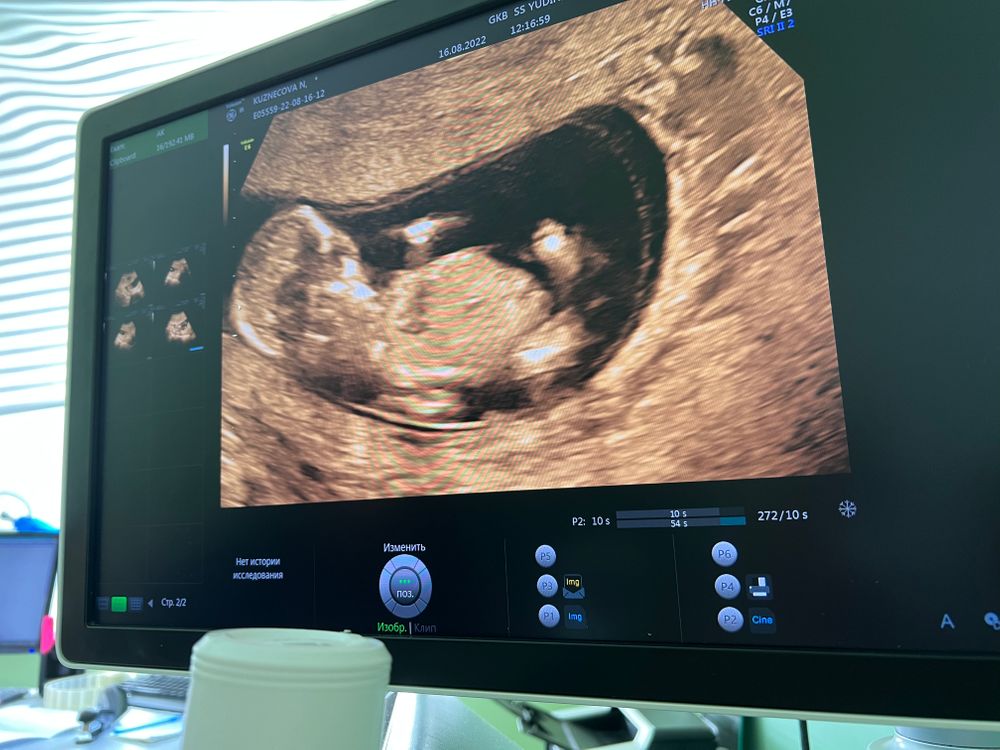

Такой пупс классный 😍ножки вытянул, лежит балдеет 😁

Анастасия, спасибо🥰 и я вместе с ним теперь балдею 😅